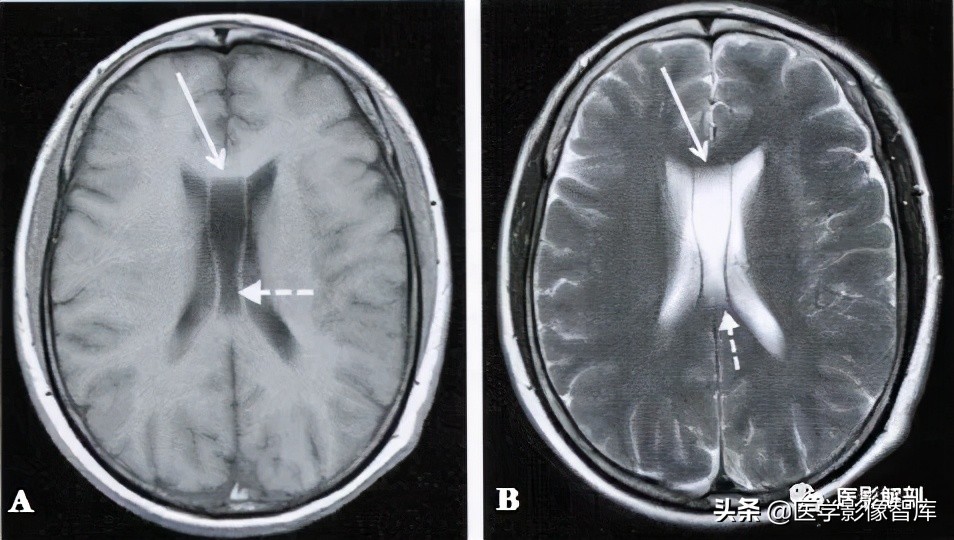

图1 第五脑室

男性,58岁。A.轴面T2WI,B.轴面T2WI。双侧的透明隔未融合,其内充满长T1、长T2脑脊液信号形(箭)。

在轴面MRI上,透明隔间腔出现在第三脑室上部层面的图像上,位于两侧侧脑室额角之间,其内为脑脊液信号,可呈条带状、三角形或类似梯形,边缘清楚,两侧壁多平行,向后直抵侧脑室室间孔(图1)。位于透明隔两侧壁之间的腔隙宽度至少要>1mm且<10mm,才可称其为透明隔间腔。

男性,40岁。A.轴面T1WI,B.轴面T2WI。在双侧脑室体部之间可见一个条形腔隙,内部充满长T1、长T2信号影,两侧的薄膜将其与侧脑室的脑脊液信号 相隔,腔隙的前部为第五脑室(长箭),后部为第六脑室(虚箭)。